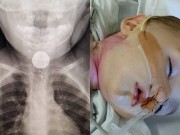

Trẻ ho có đờm đi kèm rất nhiều triệu chứng khác nhau (Ảnh minh họa)